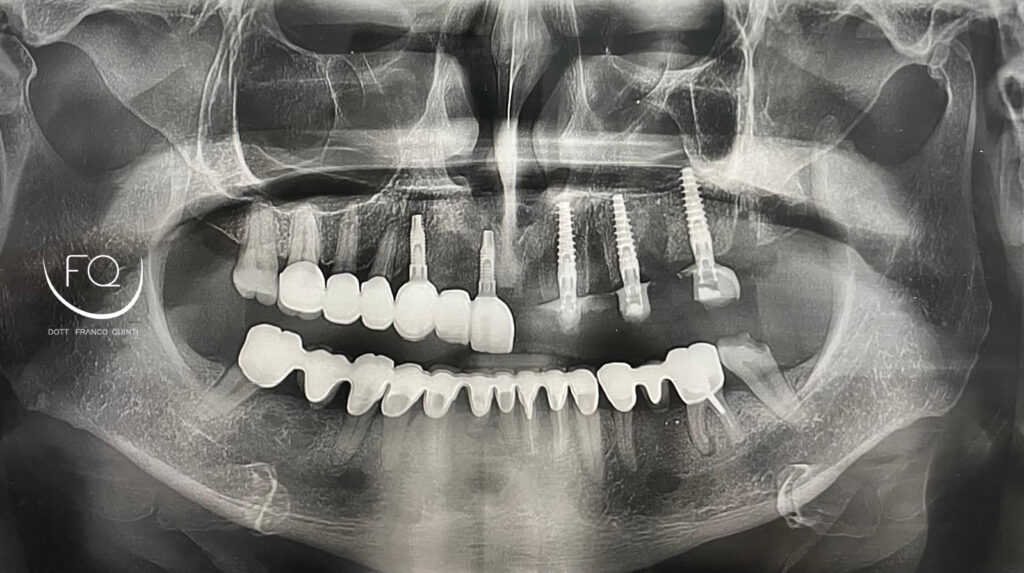

Questa settimana vi presento un caso di chirurgia computer guidata monolaterale, eseguito con l’utilizzo di una dima scomponibile ad appoggio dentale.

Durante l’intervento sono stati inseriti tre impianti PRAMA 3.8 × 11.5 di Sweden & Martina, successivamente sottoposti a carico immediato.